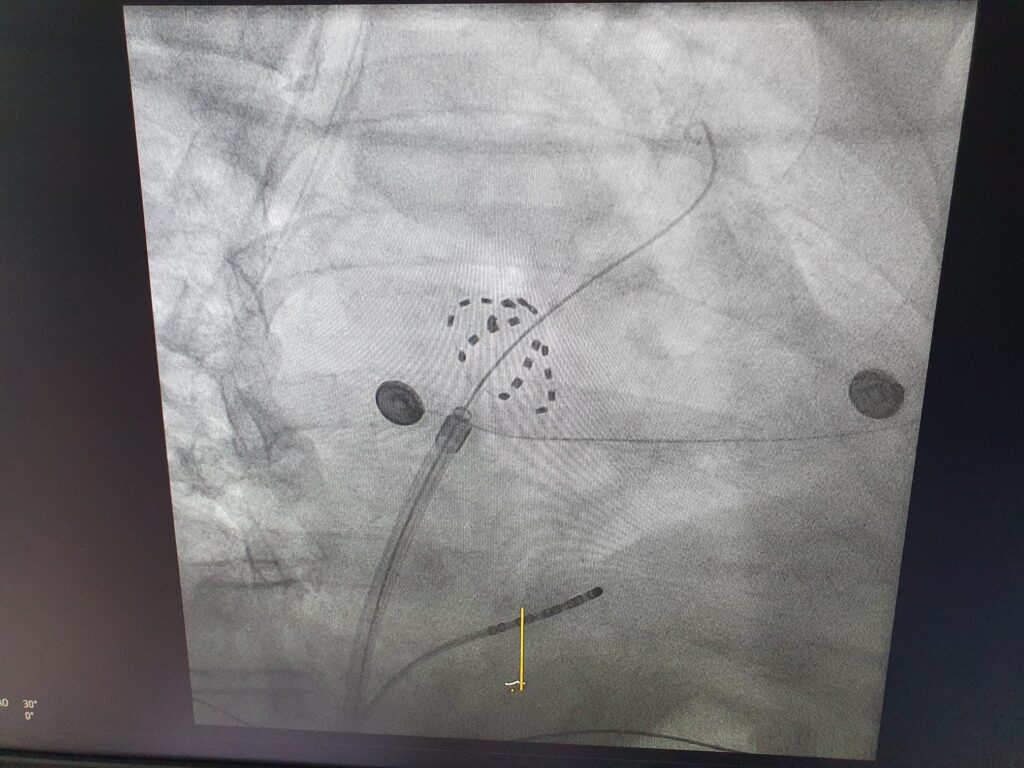

W dniu 24 kwietnia z powodzeniem przeprowadzono pierwsze zabiegi ablacji migotania przedsionków z wykorzystaniem najnowocześniejszej technologii elektroporacji.

W dniu 24 kwietnia z powodzeniem przeprowadzono pierwsze zabiegi ablacji migotania przedsionków z wykorzystaniem najnowocześniejszej technologii elektroporacji. To ważny krok w kierunku dalszego rozwoju nowoczesnych metod leczenia zaburzeń rytmu serca, który znacząco podnosi poziom bezpieczeństwa i komfortu naszych pacjentów.

Elektroporacja to innowacyjna metoda leczenia arytmii serca, polegająca na dostarczaniu krótkich impulsów elektrycznych o wysokim napięciu, które selektywnie uszkadzają komórki mięśnia sercowego w miejscu ognisk arytmii, jednocześnie oszczędzając otaczające, niesercowe tkanki — takie jak nerwy czy przełyk. Dzięki takiemu mechanizmowi działania, procedura ta jest nie tylko wysoce skuteczna, ale także szybka, precyzyjna i wyjątkowo bezpieczna, z bardzo niskim ryzykiem powikłań.